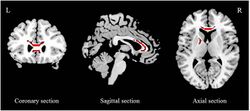

Rendition of the Limbic-cortical-striatal-pallidal-thalamic circuit as described by Drevets et al. 2008

[73]

A neuroanatomical model called the limbic-cortical model has been proposed to explain early biological findings in depression. The model attempts to relate specific symptoms of depression to neurological abnormalities. Elevated resting amygdala activity was proposed to underlie rumination, as stimulation of the amygdala has been reported to be associated with the intrusive recall of negative memories. The ACC was divided into pregenual (pgACC) and subgenual regions (sgACC), with the former being electrophysiologically associated with fear, and the latter being metabolically implicated in sadness in healthy subjects. Hyperactivity of the lateral orbitofrontal and insular regions, along with abnormalities in lateral prefrontal regions was suggested to underlie maladaptive emotional responses, given the regions roles in reward learning.[74][75] This model and another termed "the cortical striatal model", which focused more on abnormalities in the cortico-basal ganglia-thalamo-cortical loop, have been supported by recent literature. Reduced striatal activity, elevated OFC activity, and elevated sgACC activity were all findings consistent with the proposed models. However, amygdala activity was reported to be decreased, contrary to the limbic-cortical model. Furthermore, only lateral prefrontal regions were modulated by treatment, indicating that prefrontal areas are state markers (i.e., dependent upon mood), while subcortical abnormalities are trait markers (i.e., reflect a susceptibility).[76]